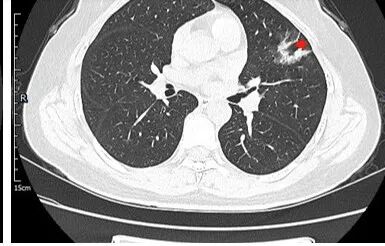

左肺上叶胸膜下不规则结节影,分叶、粗短毛刺,胸膜牵拉等,像个“刺头”。

未见钙化,也未显示液化坏死或空洞。

与支气管相关,但取层未能显示支气管进入情况。

有几点应当引起我们高度重视:

1.病灶周围向几个方向膨出的边界清楚的磨玻璃影,这些磨玻璃影时隔几个月依然,几乎可以排除出血及一般的炎性改变。

2.病灶的胸膜牵拉线与其间病灶胸膜侧的磨玻璃边构成朝向胸壁的“月牙铲”结构,这种影像学表现某种程度上反映出病理学特征——病灶收缩+小叶间隔阻挡。

3.病灶实性密度区强化明显,这有助于我们区分一些其他类似病灶,如结核灶等!

4.邻近未见树芽征及卫星灶等。

结合临床,应当高度怀疑浸润性肺腺癌!